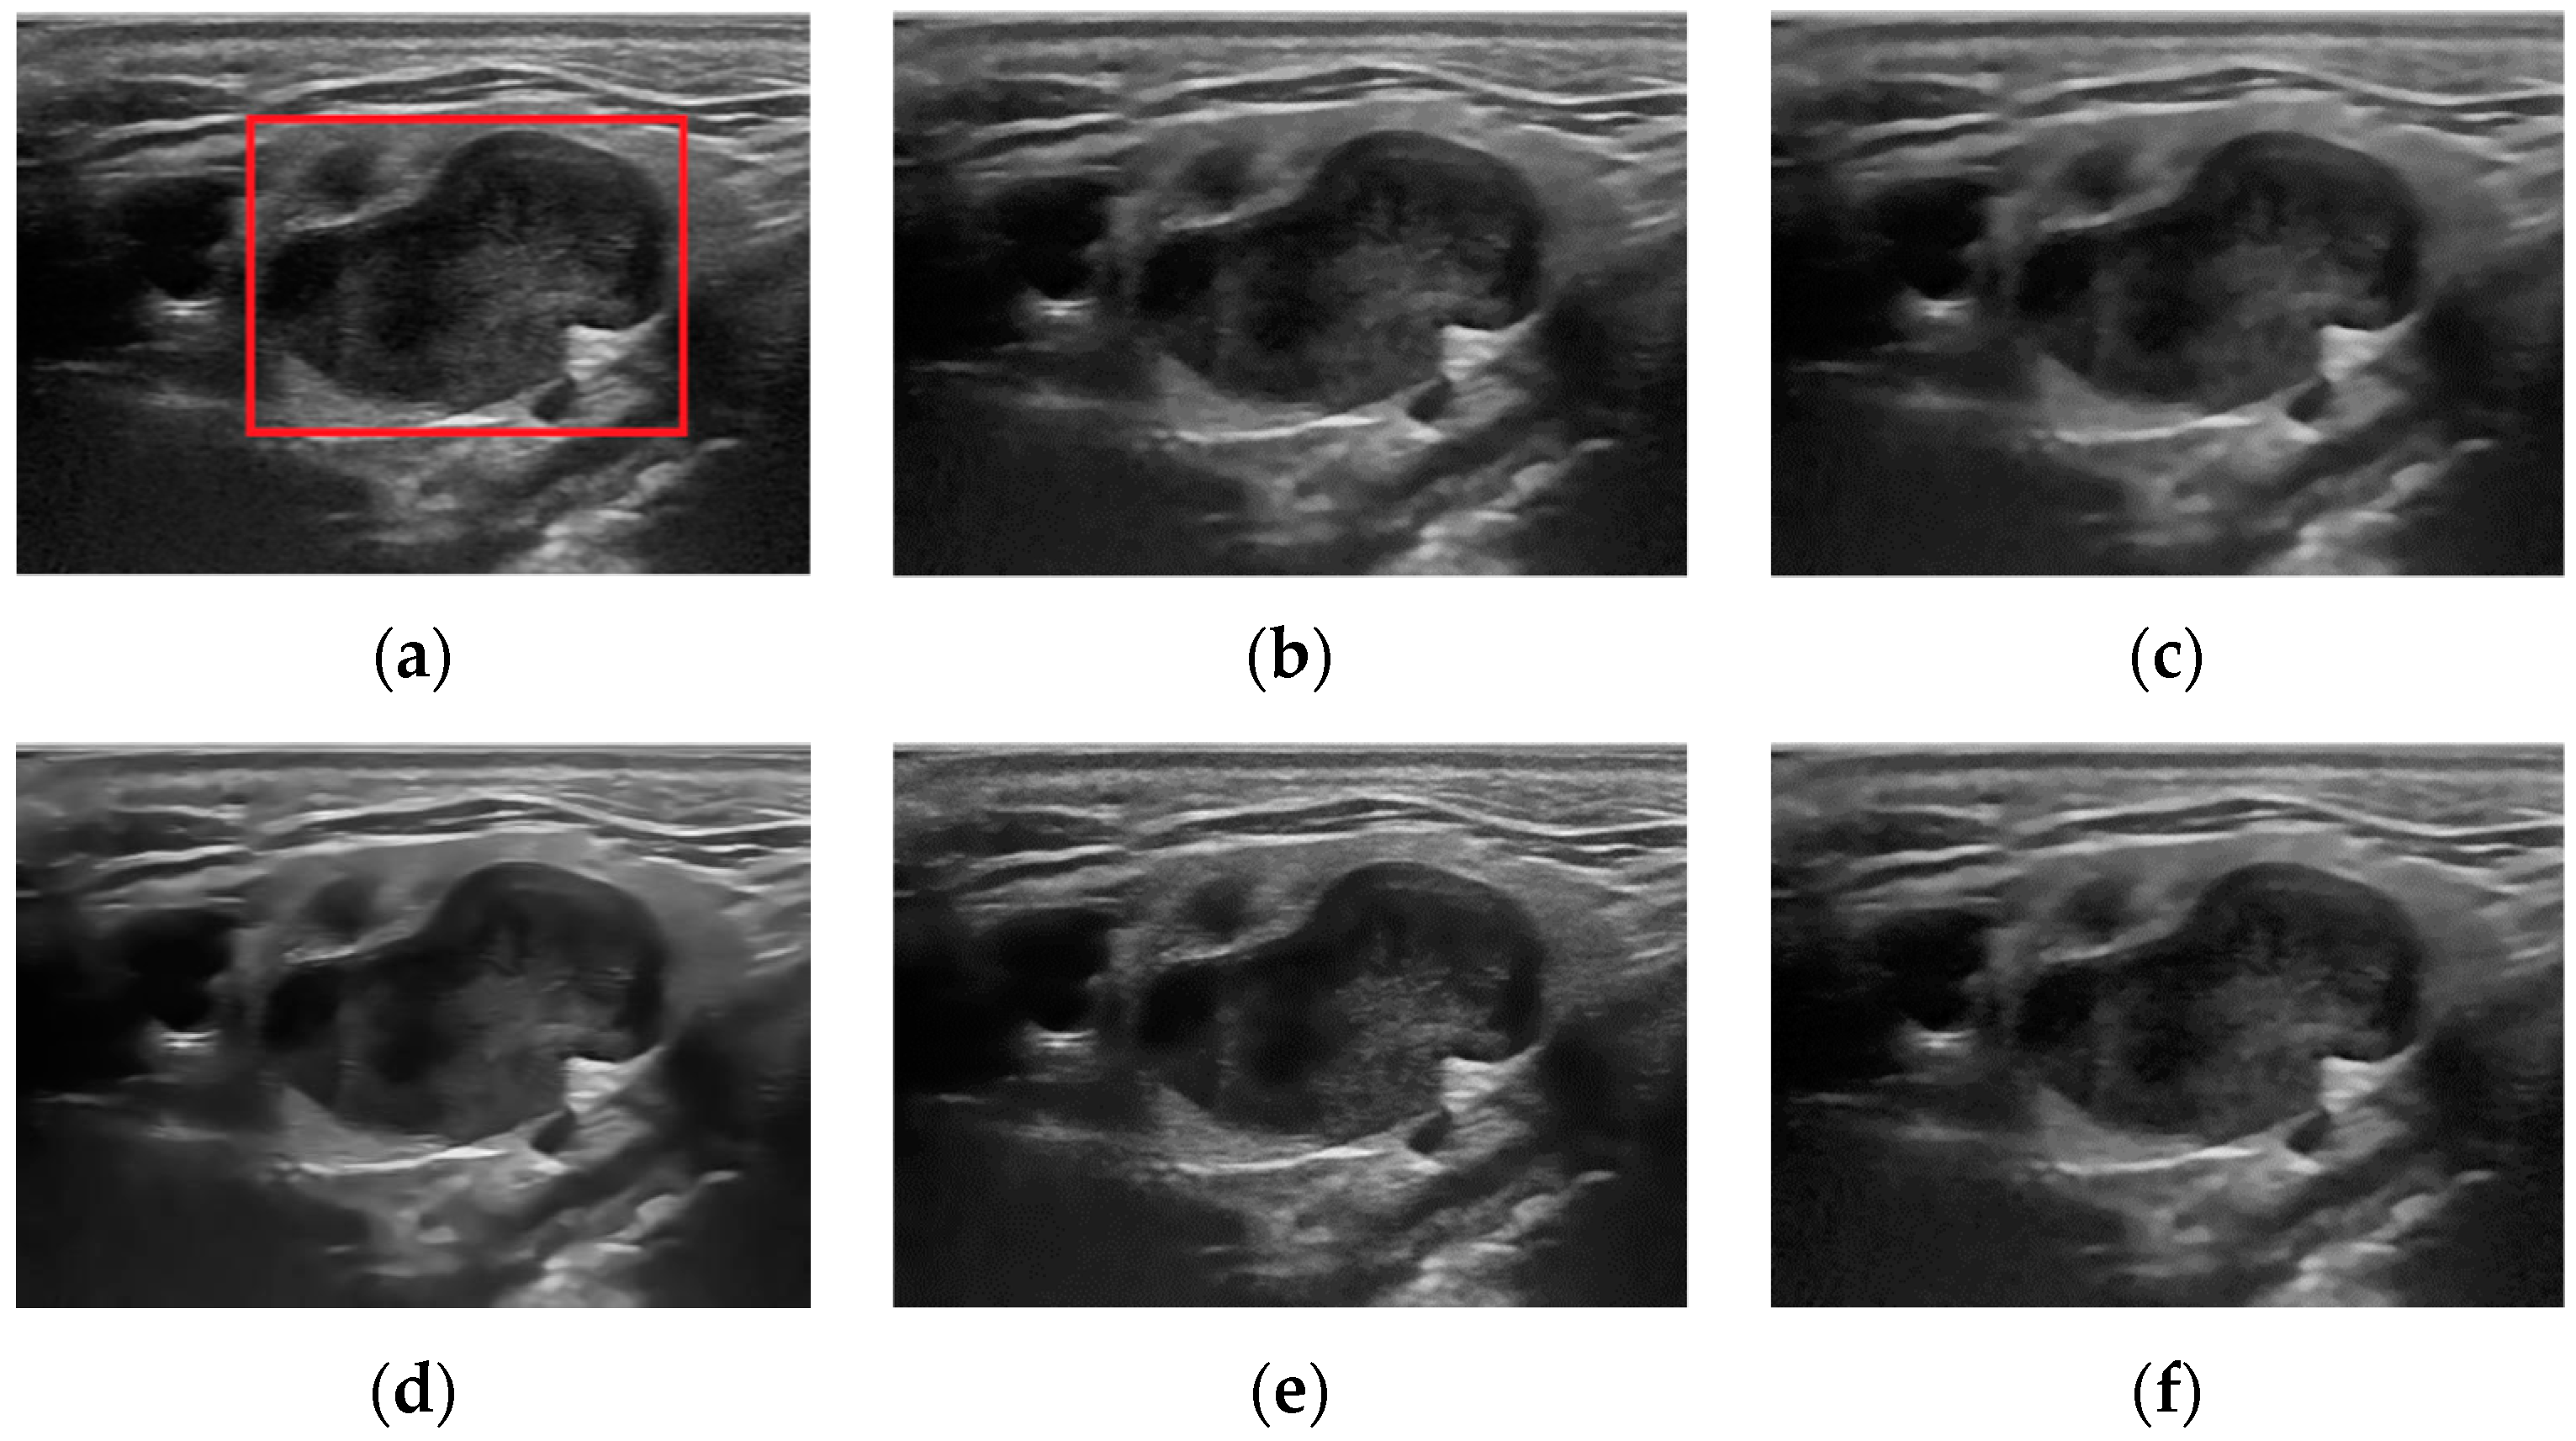

5.2. Real Ultrasound Image Denoising Experiment

5.2.2. Experimental Results